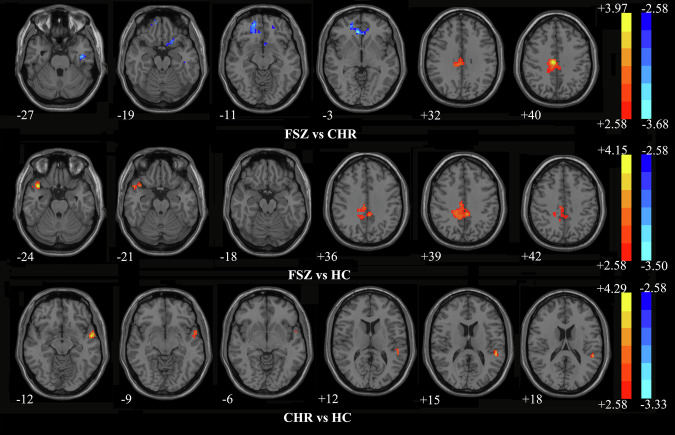

临床高危(CHR)是指精神病前的前驱期,其特征是精神病症状减弱,短暂或间歇性,功能下降。与精神分裂症相比,他们表现出眼动异常和脑功能损伤,潜在地增加了患精神病的脆弱性。本研究调查了CHR和首发精神分裂症(FSZ)个体的眼动功能障碍和脑活动改变,以确定精神病进展的早期生物标志物。招募27名drug-naïve FSZ, 25名CHR和28名健康对照(hc)进行眼动追踪任务和静息状态功能磁共振成像以评估眼动和区域均匀性(ReHo)差异。机器学习算法用于区分FSZ和CHR。结合Allen人脑图谱(AHBA),应用转录组-神经成像分析鉴定reho相关基因表达谱。FSZ在多个任务中表现出广泛的眼动异常,而CHR中已经存在某些异常。三组患者眼眶额回、颞回和扣带的ReHo异常变化与特定眼动参数有关。这些眼球运动和ReHo的差异使得它们之间的区分具有很高的准确性。遗传分析鉴定出FSZ和CHR的显著基因,丰富了各种生物学功能和途径(均校正p

Clinical high-risk (CHR) is a prodromal period before psychosis characterized by attenuated, transient, or intermittent psychotic symptoms and declining functioning. They exhibit eye movement abnormalities and brain functional damage compared with schizophrenia, potentially increasing vulnerability to psychosis. This study investigates eye movement dysfunction and brain activity alterations in CHR and first-episode schizophrenia (FSZ) individuals to identify early biomarkers for psychosis progression. Twenty-seven drug-naïve FSZ, 25 CHR, and 28 healthy controls (HCs) were recruited for eye-tracking tasks and resting-state functional magnetic resonance imaging to evaluate eye movement and regional homogeneity (ReHo) differences. Machine-learning algorithms were used to differentiate FSZ from CHR. In combination with the Allen Human Brain Atlas (AHBA), transcriptome-neuroimaging analysis was applied to identify ReHo-related gene expression profiles. FSZ exhibited a wide range of eye movement abnormalities across multiple tasks, while certain abnormalities were already present in CHR. Abnormal ReHo alterations were found in orbitofrontal gyrus, temporal gyrus, and cingulum among three groups, associated with specific eye movement parameters. These differences in eye movement and ReHo allowed for high-accuracy discrimination between them. Genetic analysis identified significant genes in FSZ and CHR, enriched in various biological functions and pathways (all corrected p < 0.05). FSZ and CHR exhibited different eye movement and ReHo patterns, indicating potential as early biomarkers. Our findings reveal correlations between these ReHo patterns and gene expression profiles using AHBA database, shedding light on possible genetic mechanisms underlying brain function in FSZ and CHR.